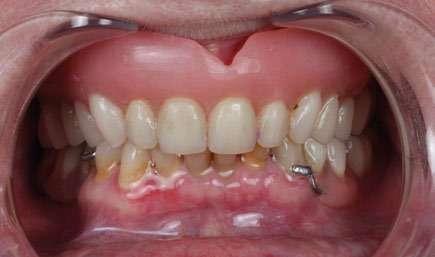

A nivel prostodóntico, decidimos abordar el caso de una manera totalmente digital con materiales monolíticos. La prótesis final es una restauración de zirconio monolítico con barra de titanio. La fusión de zirconio monolítico con barras de titanio representa una sinergia perfecta entre estética y funcionalidad. Esta combinación aprovecha lo mejor de ambos materiales, resultando en restauraciones dentales que son al mismo tiempo resistentes, ligeras y visualmente atractivas. Siendo los materiales que nos aportan una mayor biocompatibilidad con los tejidos.

Mientras que el zirconio proporciona una superficie resistente y estética, ideal para el enfrentamiento con las exigencias de la masticación diaria, el titanio ofrece un soporte subyacente que reduce significativamente el peso total de la prótesis. Estas barras de titanio son diseñadas a medida para cada paciente, asegurando un ajuste y soporte óptimos para las restauraciones de zirconio monolítico. La barra de titanio brinda una base sólida y fiable. Esto, no solo incrementa la durabilidad de la restauración, sino que también mejora la distribución de la carga masticatoria y reduce las complicaciones de fractura.

El conjunto obtiene una mayor resistencia mecánica y fiabilidad frente al empleo de interfases. Al tener un apoyo continuo en toda su superficie, se eliminan las secciones críticas que podrían causar roturas en pónticos o secciones de soporte demasiado cortas.

caso clínico

El diseño de las estructuras se realizó en el software Blender. La barra de titanio es sintero-mecanizada y la superestructura está realizada en un zirconio monolítico, multicapa y translúcido. Una vez fresado y sinterizado, se comprueba el ajuste de ambas estructuras y posteriormente se realiza un tratamiento de maquillaje con microestratificación con cerámica líquida de última generación. La parte rosa está estratificada con cerámica feldespática.

En la postproducción, se lleva a cabo un proceso de anodización del titanio, que es un mecanismo de oxidación que nos permite darle otro color. Elegimos el color dorado ya que es el más parecido a un sustrato dental y con el que menos se transparenta el metal a través del zirconio. El último paso es el cementado de ambas estructuras que se llevó a cabo con cemento de resina autopolimerizable Panavia V5. (Fig. 19, 20 y 21).

El diseño basal de la prótesis se realizó con una interfase plana, ligeramente semiconvexa con un contacto íntimo con los tejidos blandos para evitar el escape de aire, pero suficiente para poder pasar un Superfloss (Oral B) que permita la higienización por parte del paciente. El titanio y el zirconio representan los materiales ideales para estar en contacto con los tejidos gingivales pues generan una menor atracción de bacterias y se incrementa la zona de adherencia tisular por parte de los hemidesmosomas. Incluso

puede influir en la remineralización del hueso y en la mejora del tejido blando periimplantario. Se ajustó la oclusión minuciosamente para conseguir contactos homogéneos bilaterales y se comprobó que hubiera desoclusión posterior, sin interferencias en los movimientos excursivos de lateralidad y protrusiva. Por último, se instaló una férula de descarga final. Una vez finalizado el tratamiento, establecimos un programa de revisiones periódicas y mantenimiento periimplantario semestral. (Fig. 22, 23, 24 y 25).